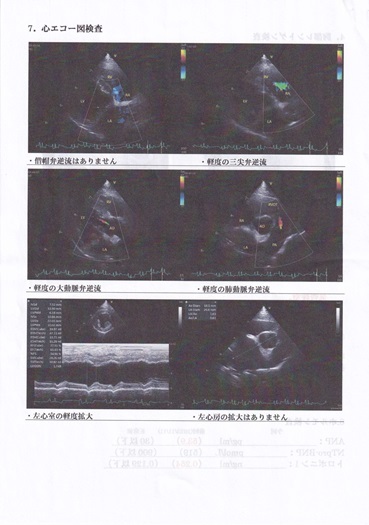

この日は僧帽弁からの逆流もなく、今まで同様3弁からの逆流は見られましたが軽度ということで心配はないとの事。前回心臓のお薬は半減されておりましたが、実はその量は飲んでいないに等しいくらいの量だったとのお話で、ついにこの日より心臓にかかわる処方はいっさいなくなり、サプリメントのみとなりました。次の受診は6か月後の6月です。投薬がなくなり喜ばしい反面不安も募ります。